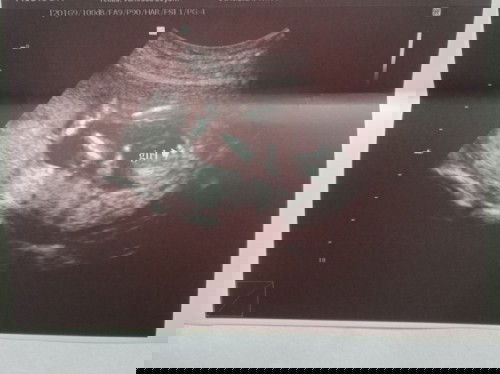

Baby's gender

Hi. I'm 16 weeks pregnant po at nagpa ultrasound na to know my baby's gender. Ganyan po ba pag baby girl? At sure na po kaya yung gender nya kahit 16 weeks palang sya? #1stimemom

Medyo hard to determine pa talaga ang gender ng baby sa 16 weeks, ang ideal for gender reveal is atleast 5months or 20weeks, di naman po ganun kalaki ang diff ng 16 tsaka 20weeks pero mas sure kase kapag 20 weeks

Mababa po accuracy pag 16 weeks pa lang?

Yup, babygirl kasi burger ang hugis. ❤️

Accurate na po kaya yang result sa ultrasound ko?